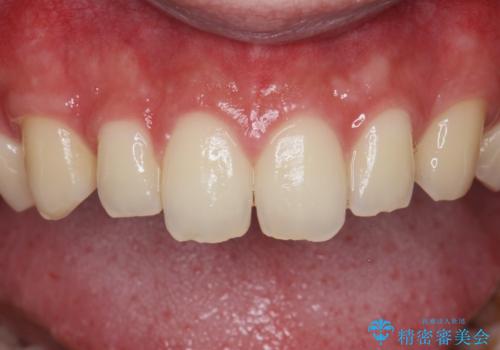

ナイトガードで歯の予防をしたい。

- 歯軋りが気になるとの事で来院。

歯が割れたりするのを予防したいとの事でしたのでナイトガードを作製しました。

ナイトガードを使用することにより歯が割れるリスクが低くなります。